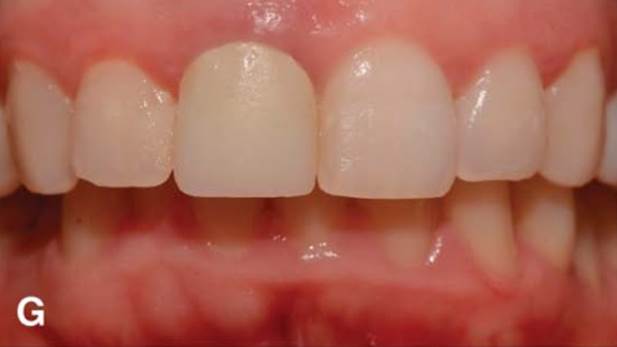

Clinical case: Replacement of fractured central incisor (#11) with immediate implant

& Root Membrane Technique

- Courtesy of Dr. Miltiadis Mitsias, Greece -

AnyRidge, Root Membrane Technique, retrospective study, long-term study, immediate implants, bone resorption, bone preservation, Dr. Miltiadis Mitsias,survival, success, maxillary anterior, single replacement

AnyRidge implant system, Root Membrane kit

The Root Membrane Technique: A retrospective clinical study with up to 10 years of follow-up./Implant Dent. 2018 Oct;27(5):564-574

https://www.ncbi.nlm.nih.gov/pubmed/30161062